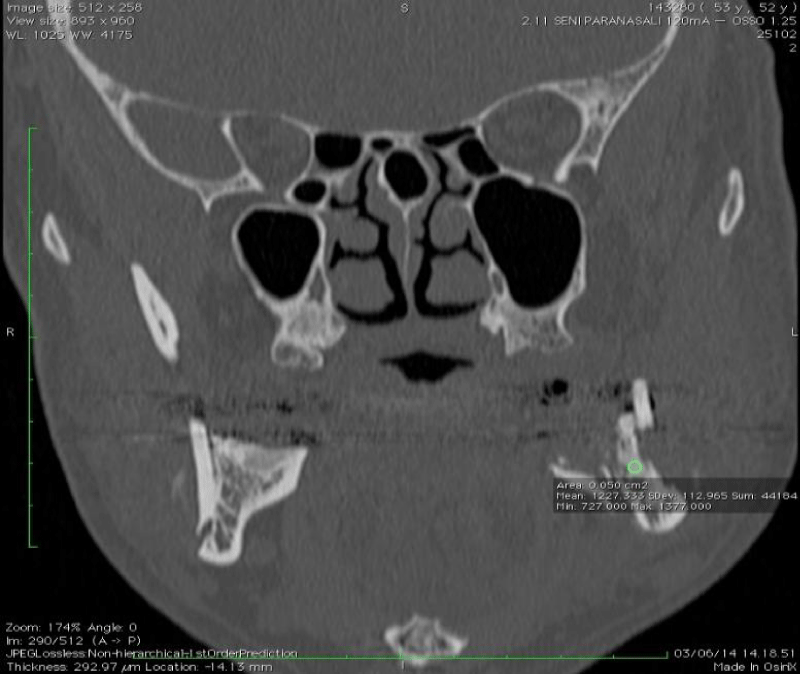

Figure 8:

Coronal CT section demonstrating fracture relationships and fixation plates.